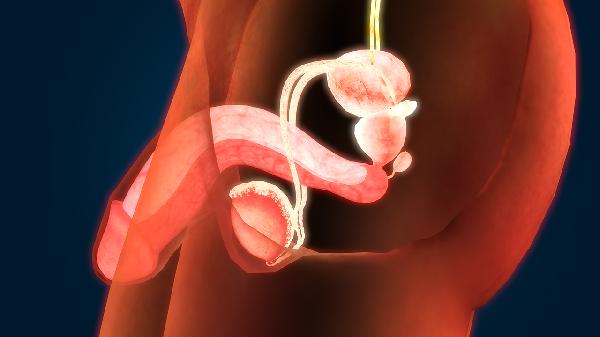

頻繁遺精可通過生活方式調整、心理疏導、飲食調理、運動干預和中醫調理等方式改善。遺精通常由生理性因素和病理性因素共同引起。

1、生活方式調整:

保持規律作息,避免熬夜和過度疲勞。睡前減少刺激性內容接觸,選擇寬松透氣的內褲,避免壓迫生殖器。控制手淫頻率,每月遺精2-3次屬正常生理現象,無需過度焦慮。

2、心理疏導:

遺精頻繁可能與焦慮、緊張等情緒相關。通過正念冥想、呼吸訓練等方式緩解壓力,避免因遺精產生羞恥感。必要時可尋求心理咨詢,認知行為療法對緩解性心理障礙效果顯著。

3、飲食調理:

減少辛辣刺激食物攝入,避免飲酒。適量食用蓮子、芡實、山藥等健脾固精食材。補充鋅元素豐富的牡蠣、堅果,維生素E含量高的綠葉蔬菜有助于調節性腺功能。

4、運動干預:

每日進行30分鐘有氧運動如慢跑、游泳,可改善盆腔血液循環。凱格爾運動能增強盆底肌群控制力,太極拳等舒緩運動有助于平衡自主神經功能。

5、中醫調理:

腎氣不固型可選用金匱腎氣丸,心腎不交型適用天王補心丹。針灸選取關元、腎俞等穴位,耳穴壓豆選取內分泌、神門等反射區。需經中醫師辨證后個性化用藥。

建立健康的生活習慣是改善遺精的基礎,建議保持適度運動,每周3-5次中等強度鍛煉,避免久坐。飲食注意營養均衡,控制晚餐進食量,睡前2小時避免進食。穿著寬松睡衣,保持睡眠環境通風。若每月遺精超過5次并伴隨腰膝酸軟、頭暈耳鳴等癥狀,建議到男科或中醫科就診排查慢性前列腺炎、精囊炎等器質性疾病。記錄遺精頻率和誘因有助于醫生判斷病情,避免自行服用補腎藥物。